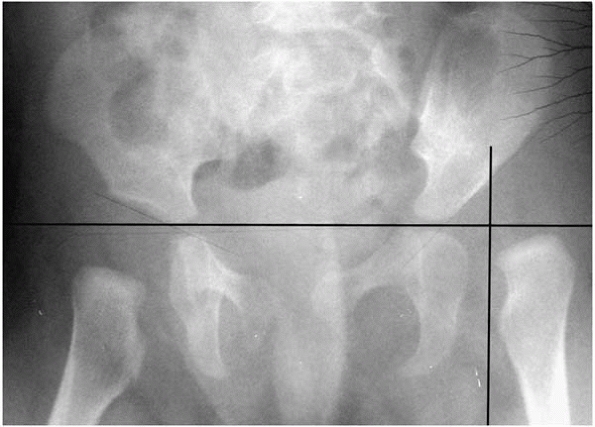

▪ FIGURE 21-2 A radiograph of a normal pelvis in a child prior to ossification of the femoral heads. A continuous “Shenton’s Line” (dotted line)

from the proximal femoral neck to the pubic bone suggests that the hips are well located. A grossly broken line is highly suggestive of a dislocated hip. An ultrasound (or MRI or CT) gives more reliable information. |

▪ FIGURE 21-3

AP radiograph of a 1-month-old girl with a dislocated left hip. The medial proximal femoral metaphysis is lateral to the Perkins line (vertical black line at lateral edge of acetabulum), demonstrating the lateral displacement of a dislocated hip. |